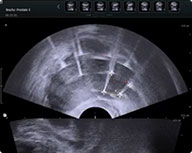

(3)测量、记录、输入针间距,系统自动生成治疗参数,执行消融治疗;

(4)完成升压后,踩脚踏开关,释放脉冲到病灶并观察实时电流;

(5)每组脉冲约 5min,完成后生成治疗报告,结束后每5mm截图;